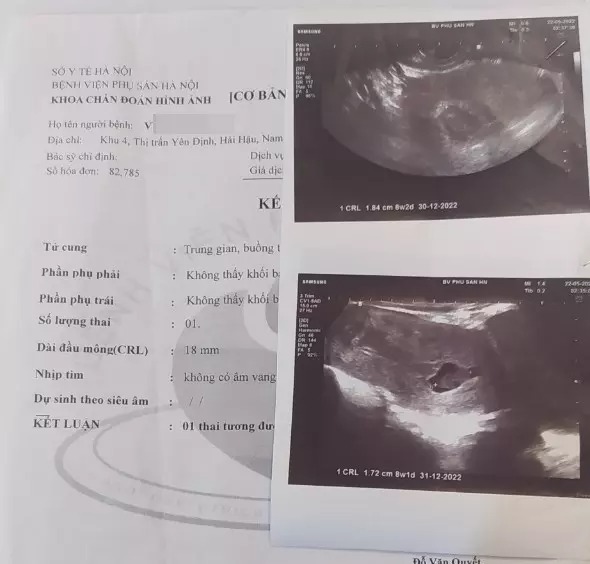

Ghi nhận của Trí Thức Trẻ, theo kết quả siêu âm, bác sĩ kết luận chị Tr "1 thai tương đương 8 tuần 2 ngày, ngừng phát triển".